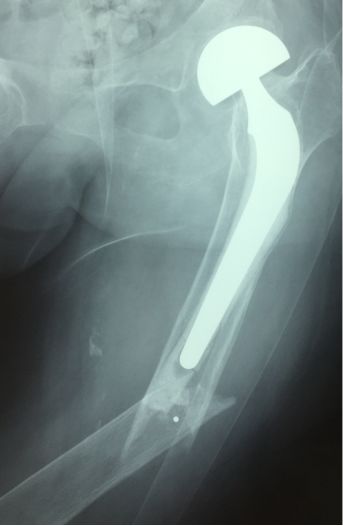

初次关节置换不好。功能差活动受限诱发进一步废用性疏松,应力集中

骨质疏松骨折选择钢板固定,应该是剥离过多骨坏死吸收。后大段异体骨移植吸收,最后失败难以收拾。开始用髓内钉会好些(理念问题)。不知道此病例结果如何?

此处应用钢板有两种情况一是不会使用髓内固定,设备条件达不到;再就是理念落后见的病例少,交流少。此处外侧全部是长应力,钢板为张力钢板,内收肌力量强大,目前的钢板不能承受反复的弯曲应力,金属疲劳断裂失败率高,以下病例切开,钢丝捆绑进一步骨膜剥离,破坏了原始血肿,干扰骨愈合,都是失败原因

补救办法:剥削植骨髓内钉固定或动力髁钢板固定。